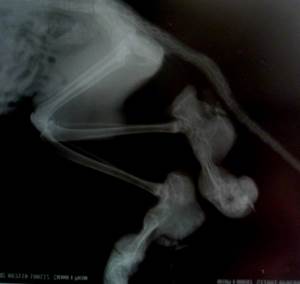

Для постановки диагноза врачу важно получить информацию о родственниках Вашей кошки, а также подробный анамнез. Проводится клинический и биохимический анализы крови, анализ мочи для исключения других причин нарушений в развитии скелета. Рентгеновские снимки пораженных конечностей покажут аномалии, связанные с ростом костей. Рентген позвоночника также покажет наличие аномалий у больных с поражением позвоночника. Чтобы подтвердить диагноз, необходимо взять образец костной ткани для гистологического исследования.